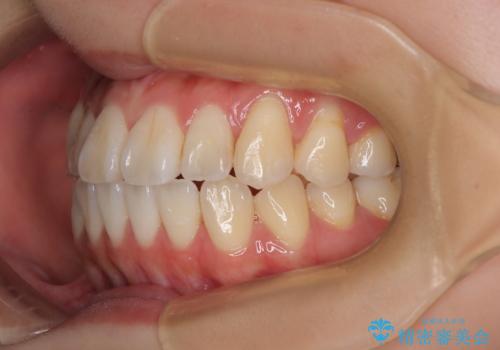

舌の突出癖が原因 インビザライン矯正による開咬改善

- 前歯の開咬を気にして来院された患者様です。

開咬の治療は、前歯を閉じるように動かすとともに、上下臼歯を圧下(骨内にめり込ませる)させることで進めて行きます。

インビザラインは臼歯の圧下を効果的に行えるため、インビザラインを用いて矯正治療を行うこととしました。

オープンバイトは舌の突出癖により誘発され、治療後も突出癖が残っている容易に後戻りしてしまいます。

治療期間を短縮するためにも、舌突出癖の改善が極めて重要となります。

特にインビザラインではIPRという歯と歯の間を削る処置を多用するため、後戻りによりスペースが生じやすくなるため、治療初期段階での舌のトレーニングが必須となります。